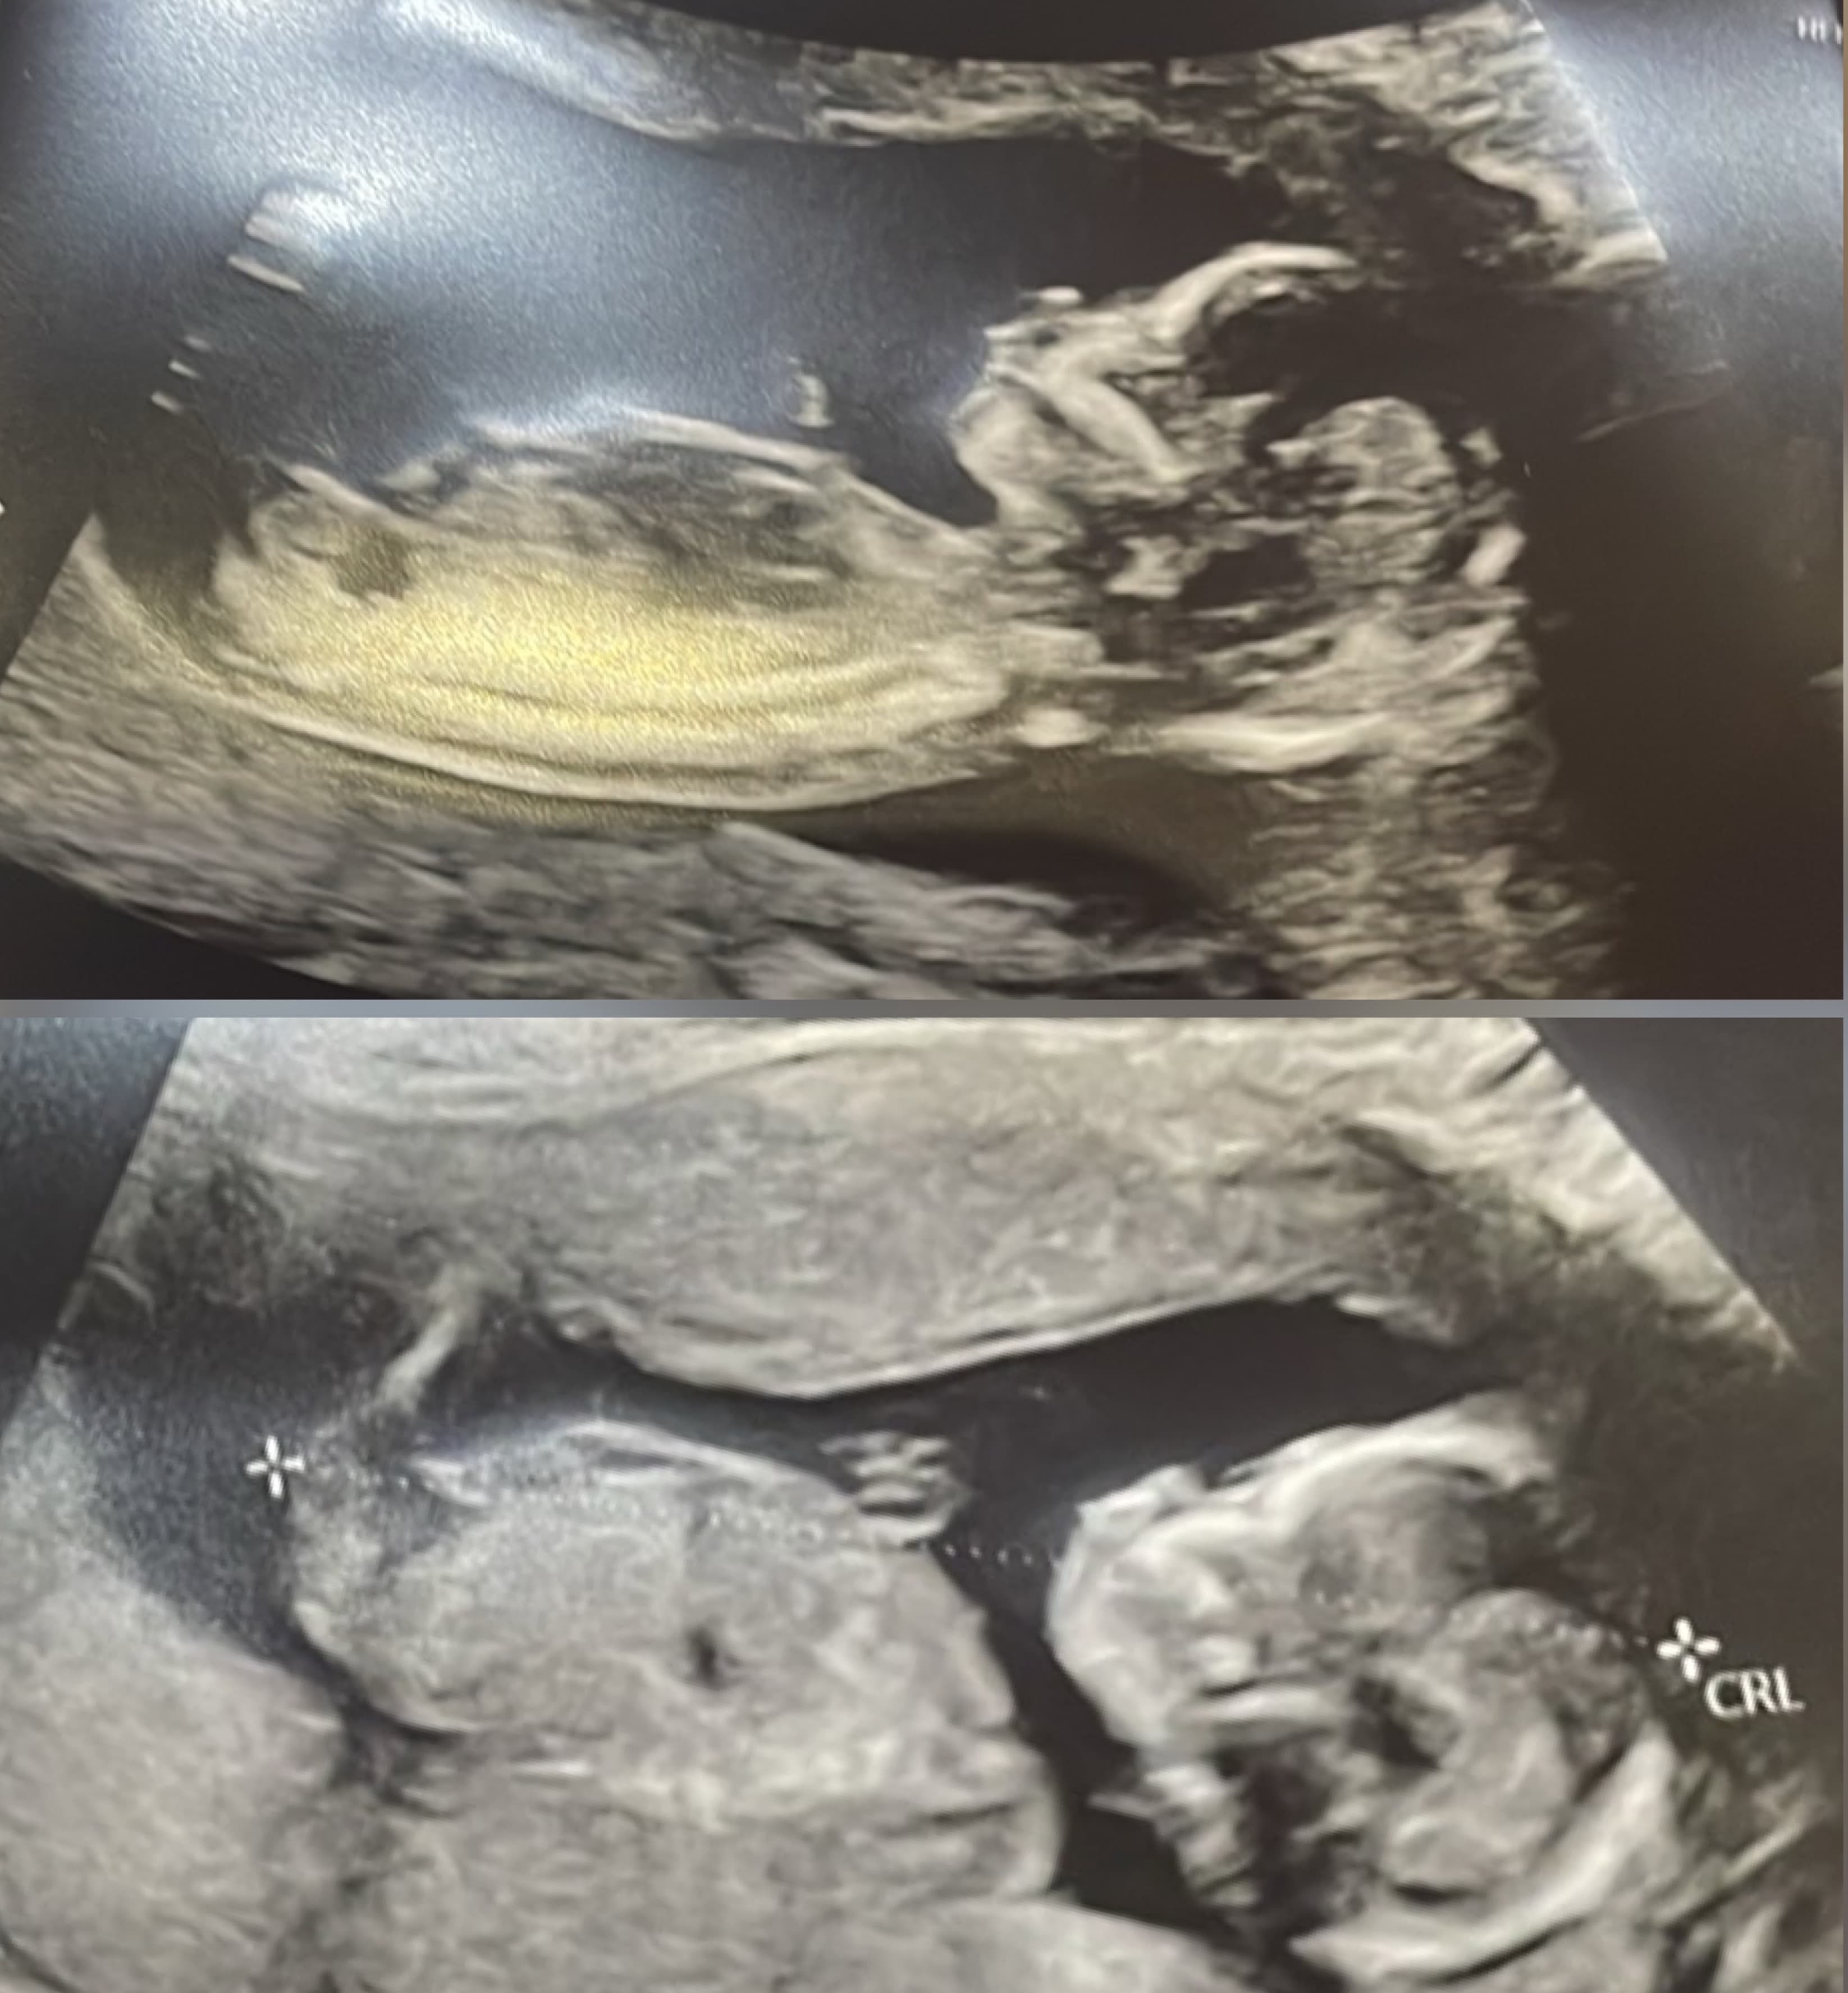

Christoff & Christopher would have been born on January 8, 2026 to the late Christopher Fuller & Raquel Rooks-Fuller. Despite their short time on earth, they were deeply loved and brought immense joy to those around him. >Christoff & Christopher will be forever remembered and loved by their surving parent Raquel Rooks-Fuller, Grandparents ( Greggory& Jeanie Rooks & Anthony & Sharonda Fuller), Loving Aunts (Sherice, Jerrica, Emily, Anita, Cathy), Uncles (Andrew, Levi, Jason, Duran), and a host of cousins and loving family members.

Christoff & Christopher's Photos

Select a photo to expand it and view its comments.